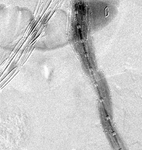

Resolución de la endofuga tipo I, resuelta con la expansión de la extensión

University of Michigan, específicamente los casos del Dr. Upchurch que reflejan los Departamentos de Cirugía Vascular y Radiología